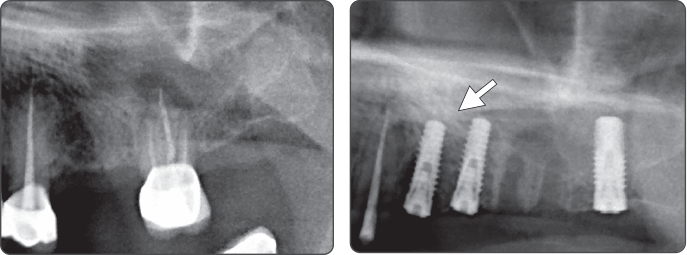

Sequence -Sinus Lift

Only use of Sinus Lift Drill

1. Sinus Lift (Ø4.0 Fixture)

▶ Immediate Implantation and Sinus Lift Technique with Tap Drill (Ø4.0 Fixture)